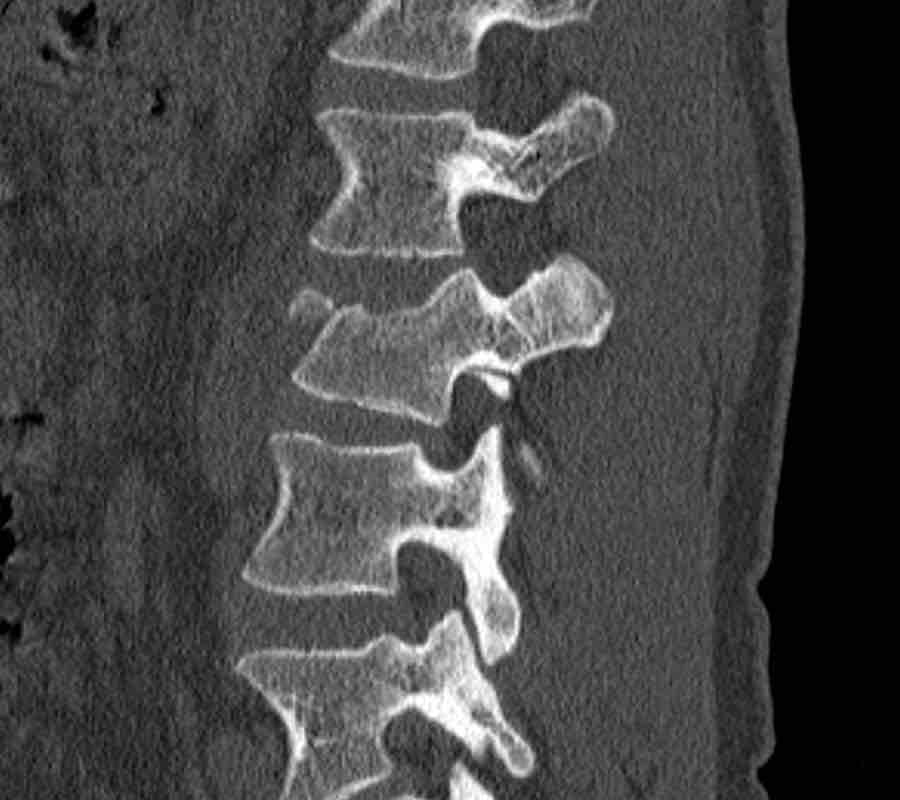

What is the highest AO-type of injury?

Findings:

- No C or B injury

- Fractures of the vertebral body with involvement of both endplates (1+1 points) and posterior wall (2 points)

Conclusion

Injury type A4